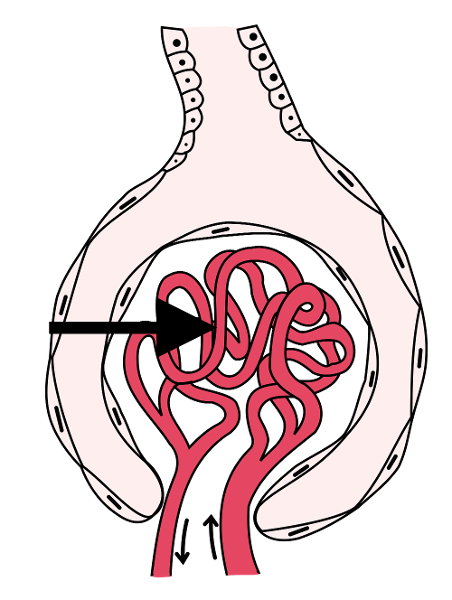

Afferent/efferent arteriole

Glomerular capsule (=Bowman's capsule)

Glomerulus (=glomerular capillaries)

Juxtaglomerular apparatus

Peritubular capillaries

Renal corpuscle